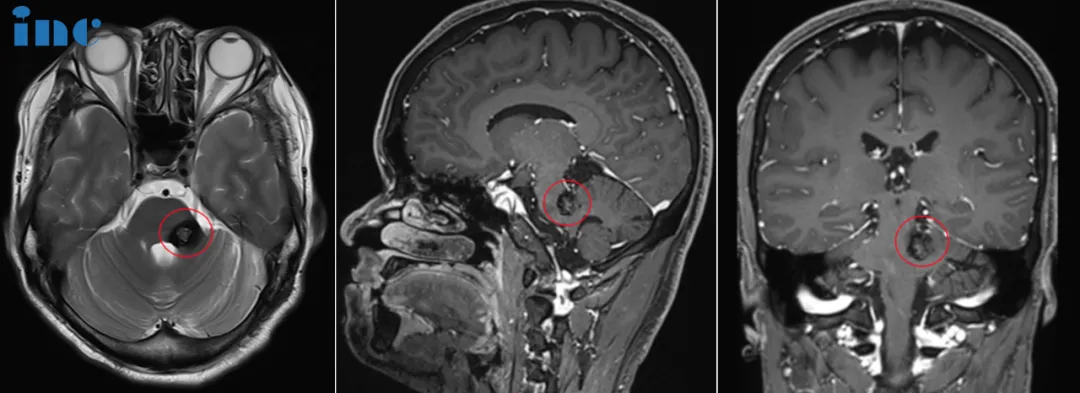

伽马刀治完不仅没好,走路越来越费劲,复查还说病灶变大了2022年,林女士拿着最新的MRI报告,满心焦虑。 两年前,她因运动后突发头晕、左腿疼痛查出脑干海绵状血管瘤,为降低风险选择伽...